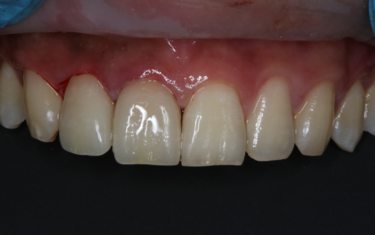

Figures 6 and 7 (below): The patient one-year later confirmed marginal integrity of the two crowns and success of the root canal therapy.